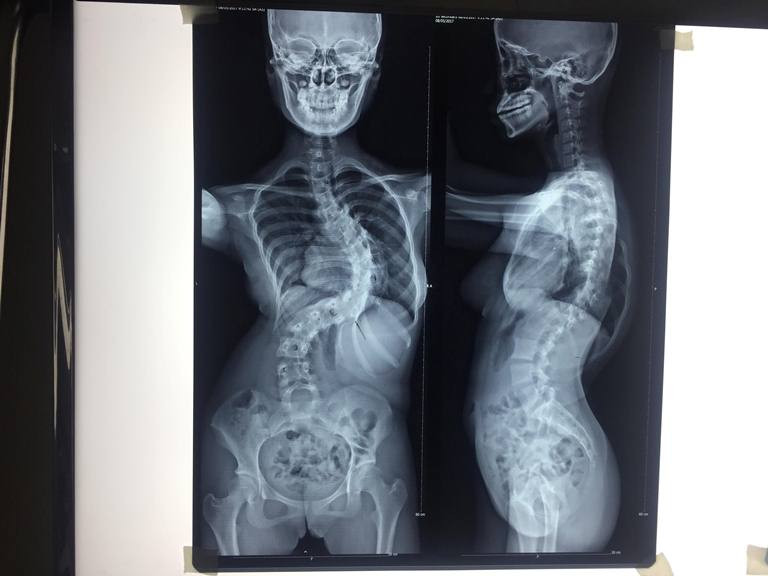

Hình chụp cột sống của bệnh nhân trước và sau phẫu thuật

Bệnh nhân nhập viện trong tình trạng khó thở, đau lưng nhiều và không thể ngồi lâu được. Qua thăm khám, GS Thành nhận định bệnh nhân bị vẹo cột sống do hội chứng Marfan (hội chứng tổ chức liên kết mang tính di truyền),vẹo thành 3 đường cong lớn góc vẹo lên đến 110 độ. “Trước đây tại BV từng phẫu thuật một ca tương tự, nhưng góc lệch chỉ có 69 độ”, BS CKII Hồ Nhựt Tâm( Trưởng đơn vị cột sống BV Trưng Vương) cho biết.

Cột sống của bệnh nhân vẹo đến 110 độ, chia thành 3 đoạn

Ca mổ diễn ra gần 7 giờ đồng hồ, ê kip phẫu thuật đã đặt 21 ốc chân cung bằng titan, vừa hàn xương nhằm nắn lại cột sống cho bệnh nhân 15 tuổi này.

Sau phẫu thuật, hiện tại sức khỏe của bệnh nhân đã ổn định, có thể đi lại xung quanh phòng. “Ca phẫu thuật đã nắn chỉnh cột sống bệnh nhân từ 110 độ xuống còn hơn 40 độ, tỷ lệ nắn chỉnh lên đến 60%. Sau phẫu thuật, chiều cao bệnh nhân tăng lên 7cm.”, BS Tâm cho biết thêm.